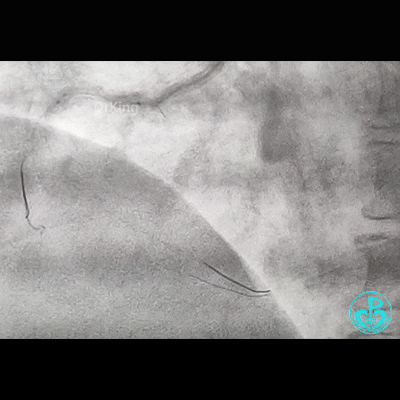

冠脉造影

右锁骨下动脉迂曲打圈,影像如下:

病变简单吧!